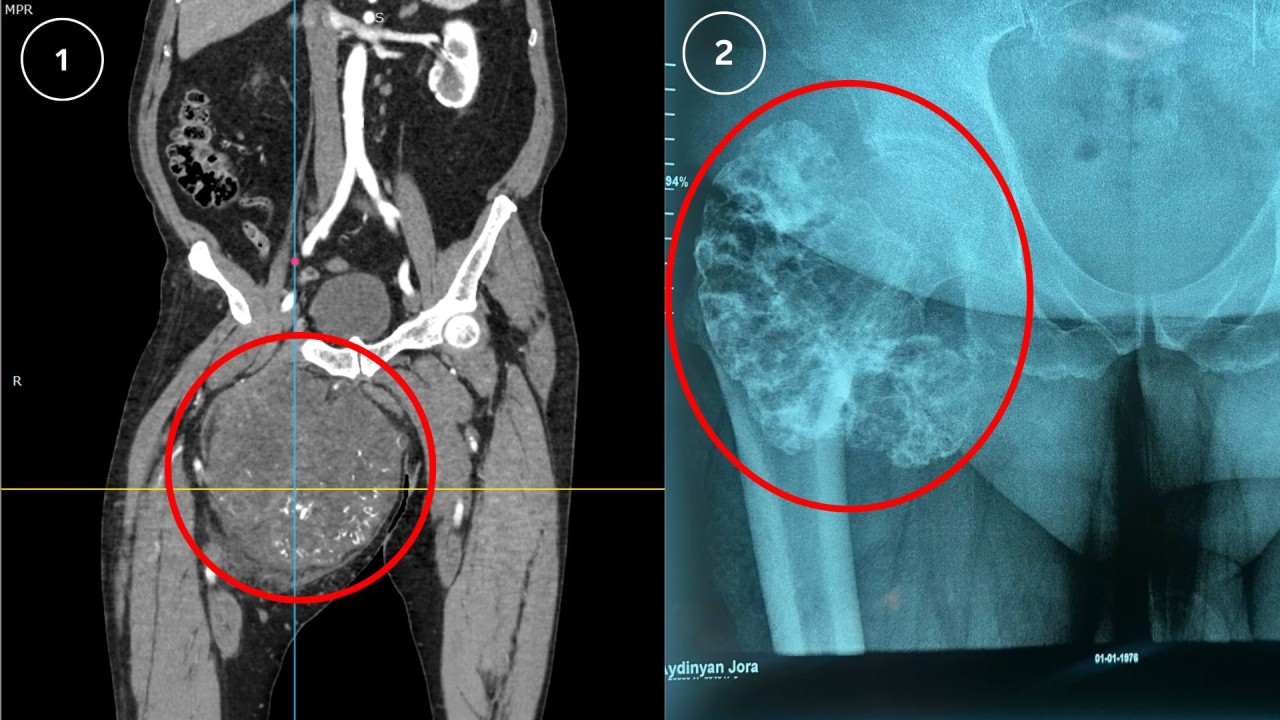

Բացառիկ վիրահատություն․ հսկայական խոնդրոսարկոմա ուռուցքի հեռացում

Ուռուցքաբանության ազգային կենտրոնի Ս. Սեինյանի անվան հենաշարժիչ համակարգի ուռուցքաբանության բաժանմունքում վերջերս կատարվել են երկու բարդ և ծավալուն վիրահատական միջամտություններ, որոնք առանձնանում են